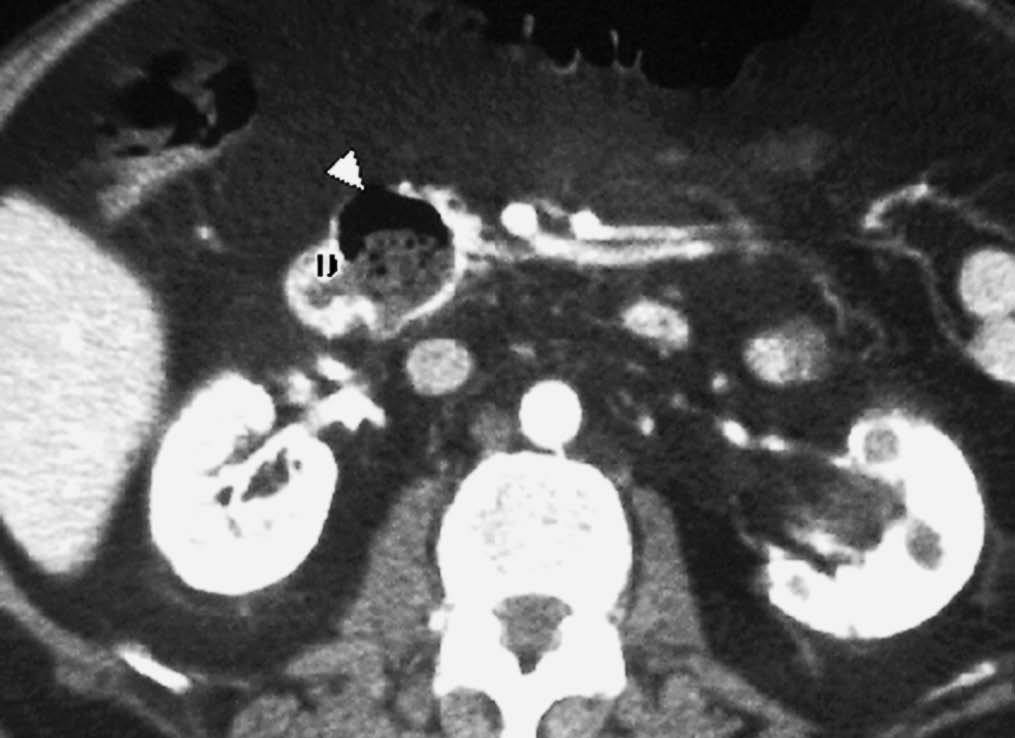

Los divertículos duodenales son prominencias saculares en contacto con la luz intestinal. Por su alta frecuencia pueden considerarse una variante de la normalidad. Se localizan principalmente en la pared medial de la segunda y tercera porción duodenales, próximos a la ampolla de Vater. Las complicaciones más frecuentes son la infección, perforación, hemorragia, pancreatitis o la obstrucción biliar. Es importante identificarlos, pues pueden dificultar la canulación de la vía biliar durante la colangiopancreatografía retrógrada endoscópica (CPRE). Ecográficamente se presentan como imágenes hiperecogénicas lineares o cóncavas, proyectadas sobre la cabeza pancreática7. En la TC se manifiestan como estructuras redondeadas o saculares, en contacto con la luz duodenal, rellenas de líquido, aire o con un nivel hidroaéreo8 (fig. 2). Cuando están rellenas de material pueden simular una masa pancreática, por lo que hay que buscar aire en su interior.

Fig. 2--Divertículo duodenal. Tomografía computarizada con contraste intravenoso. Se observa una estrucutra sacular (punta de flecha) en contacto con luz duodenal (D), con aire y material en su interior.